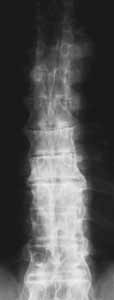

- cervical spine x-ray (lateral)

- lumbar spine x-ray (lateral)

- thoracic spine x-ray (lateral)